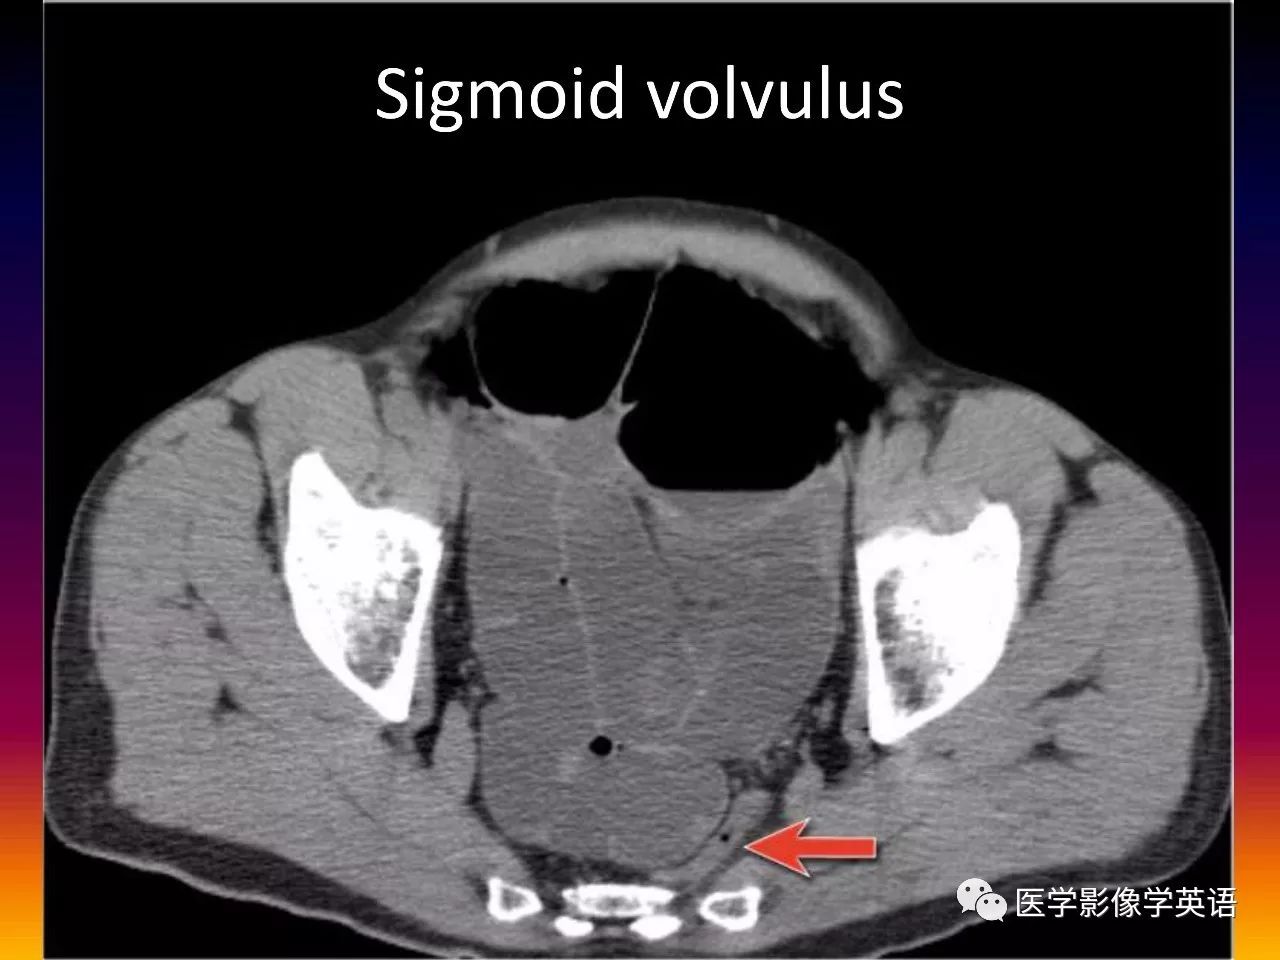

85. Sigmoid volvulus

86. Sigmoid volvulus

87. Sigmoid volvulus

88. Sigmoid volvulus

89. Sigmoid volvulus

90. Sigmoid volvulus

91. Sigmoid volvulus

92. Sigmoid volvulus